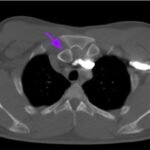

Posterior sternoclavicular dislocations are very rare and pose immediate threat to mediastinal structures should a patient sustain this type of injury. This case report discusses the presentation and diagnosis of a young male who presented with isolated right arm swelling after blunt trauma one day prior while participating in a bull riding rodeo event. He was diagnosed with posterior right sternoclavicular joint dislocation with compression of the left brachiocephalic vein that was seen on computed tomography (CT) angiogram study. Patient was transferred to a tertiary care center for a higher level of care and definitive reduction management. Any history of blunt shoulder trauma or direct sternoclavicular trauma with symptoms to suggest compression of mediastinal structures should make one suspicious for posterior sternoclavicular dislocation. Evaluation is best made by computed tomography (CT) scan. Reduction should be performed by an orthopedic surgeon in the operating room with cardiothoracic surgery available for any vascular compromise that may occur.